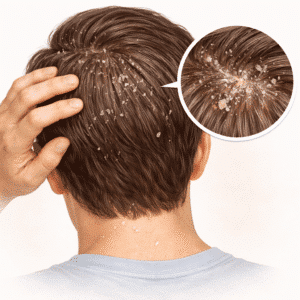

Dandruff & Scalp Care

Understanding Dandruff & Scalp Care Dandruff is a common condition…

Dandruff & Scalp Care: A Simple Guide to a Flake-Free, Healthy Scalp

Dandruff is one of the most common scalp concerns, yet it is…